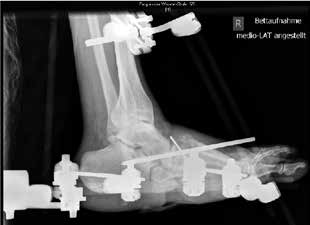

Die Art und Weise einer adäquaten operativen Therapie wird stark kontrovers diskutiert. Nach Auffassung der Verfasser ist die externe Fixation ein geeignetes, effektives und äußerst variables Verfahren mit relativ geringer Komplikationsrate. Es können sowohl aktive als auch inaktive Osteoarthropathien mit einem Fixateur externe behandelt werden. In der Regel wird eine Arthrodese oder zumindest eine straffe und belastbare Pseudarthrose hergestellt, die eine schmerzfreie Mobilisation unter Vollbelastung ermöglicht.

Das Versorgungskonzept bei der operativen Schiene ähnelt dem konservativen Konzept. Die Fixateur-externe-Therapie wird für 6 bis 12 Wochen durchgeführt. Die Verfasser ziehen 8 bis 12 Wochen vor, die Therapiedauer ist aber abhängig von der Compliance und der Mitarbeit des Patienten und kann sich auf ein Minimum von 6 Wochen reduzieren. Anschließend hat sich eine Versorgung in einer Unterschenkelorthese für weitere 3 bis 9 (12) Monate bewährt. Ist es zu einer knöchernen Konsolidierung bzw. straffen Pseudarthrose gekommen, kann der Patient mit orthopädischen Maßschuhen versorgt und mobilisiert werden.

Das operative Verfahren im Einzelnen

Der operative Zugang erfolgt abhängig von der Lokalisation der Charcot-Arthropathie. Bei ausgeprägten Deformitäten ziehen die Verfasser einen bilateralen Zugang vor. Neben einer sorgfältigen Entfernung avitalen Knochengewebes erfolgt gegebenenfalls eine Resektion infizierten Gewebes sowie eine Abtragung von Pseudoexostosen. Die alleinige Abtragung von Pseudoexostosen kann in einigen Fällen als alleinige operative Behandlungsmethode ausreichend sein. Bei vorhandenen Ulzera bzw. Infektionen werden gentamicinhaltige Antibiotikaträger appliziert. Autologe Spongiosa bzw. Knochenersatzstoffe können in die restlichen Defekte nach Reposition und Anfrischung der Gelenkpartner interponiert werden. Fixateur-Pins mit zentralem Gwinde werden in die Metatarsaliaköpfchenreihe, den Calcaneus und die Tibia eingebracht. Nach Reposition des Fußes wird der Fixateur externe montiert, in der Klinik der Verfasser der Hoffmann-II-Fixateur als bilaterale Rahmenkonstruktion (Abb. 4). Zielvorgabe für die dreidimensionale Stellungskorrektur ist hierbei die lotgerechte Einstellung des Fußes in der frontalen Ebene mit plantigrader Belastbarkeit (Abb. 5a u. b). Während der Tragedauer des Fixateurs erfolgt eine vollständige Entlastung der betroffenen Extremität. Der Patient ist für diese Zeit im Rollstuhl oder bestenfalls an Unterarmgehstützen mobilisiert. Sechs bis zwölf Wochen postoperativ wird das Material entfernt. Die vollständige Materialentfernung kann ohne Narkose unter Analgesie durchgeführt werden. Bis zur Versorgung mit einer Orthese wird der Fuß vor der Überbelastung des reponierten Fußes mit einem Cast geschützt.